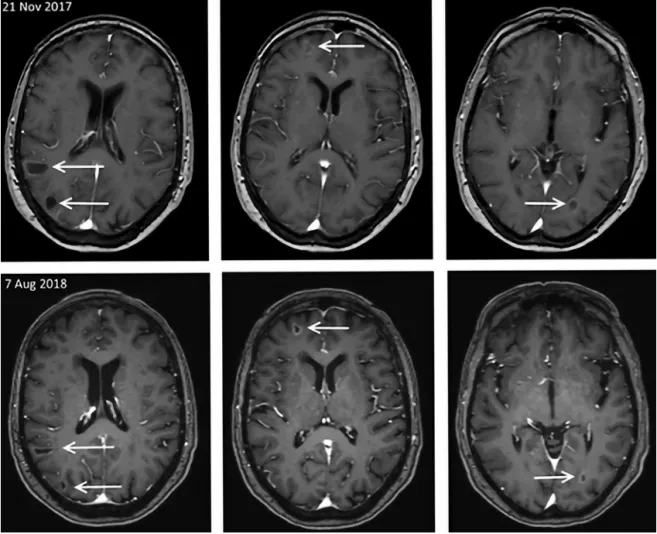

数天后,患者视力下降,转诊眼科。检查发现一个非色素性脉络膜视网膜肿瘤,很可能与乳腺癌转移相关,导致浆液性脱离。MRI显示至少有5个脑转移瘤和1个眶内转移瘤,视网膜增厚与眼科报告相符,还有1个颅骨转移瘤。

2个月后随访的第一阶段显示治疗有效,肺和肝转移瘤的大小均缩小了50%以上。头部MRI显示脑转移瘤稳定,视网膜转移灶缩小50%以上。患者恢复正常视力后无症状,无呼吸困难。因此,阿那曲唑和ribociclib的治疗仍在继续。

一阶段8周后的第二阶段,包括脑转移在内的所有转移灶体积均缩小(表1);眶内转移灶完全缓解(图1)。病人自述生活质量非常好。

表1.治疗3.5个月后,脑实质转移瘤的大小

3个月后,放射科医生针对头部MRI描述了部分脑转移瘤进一步缩小,部分病情稳定。患者在临床上仍能很好地耐受治疗,没有任何症状。因此仍继续治疗。

开始治疗近9个月后,行胸部和腹部CT以及头部MRI分期,结果显示:除肺和脑的病情稳定(图2),肝脏(8×10 cm)(图3)和颅骨观察到病情明显进展。肝活检证实激素受体阳性(ER 80%,PR 10%)和HER2阴性的乳腺癌转移,Ki-67为25%。就进一步的治疗方案与患者交流,并建议更换药物。患者因担心脑转移瘤希望继续使用ribociclib和芳香化酶抑制剂进行治疗,而在整个治疗过程中,脑转移瘤一直状态稳定。由于患者一般情况恶化,停止服用ribociclib,单独继续服用阿那曲唑。2个月后,下一阶段结果显示显示:除大脑外,所有转移部位都有进展性疾病。行肝动脉化疗栓塞术治疗肝转移瘤后,开始紫杉醇化疗。3个周期化疗的临床疗效良好,肝、肺部分缓解,脑部病变稳定。

图2.实质性脑转移瘤MRI分期表现